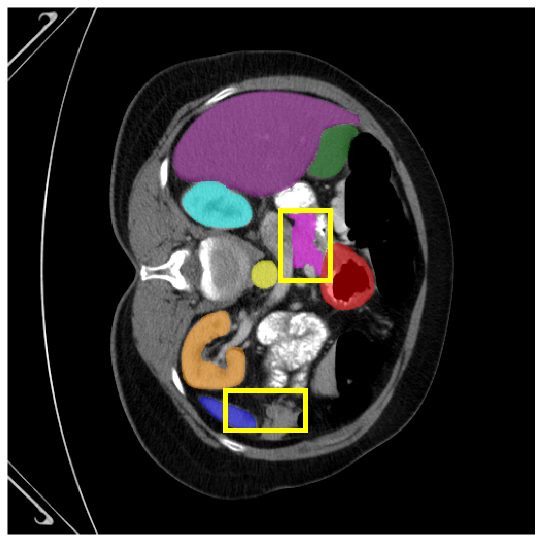

4.3.2 Visual Comparisons

Visualization of our method on the Synapse and ACDC datasets is shown in Fig. 3(a) and Fig. 3(b). For the Synapse dataset illustrated in Fig. 3(a), FCT failed to accurately segment SM and GB, while MERIT achieved precise segmentation of SM but struggled with GB. In contrast, our method achieved accurate segmentation of both SM and GB. Regarding the ACDC dataset shown in Fig. 3(b), while previous methods achieve comparable segmentation of the Myo and LV to the GT, they exhibit noticeable errors on the RV, including invasion into adjacent organs and misrecognition. On the other hand, our method accurately segments across all three structures Myo, LV, and RV, performing as precisely as the GT. We demonstrate the superiority of our method quantitatively and qualitatively.